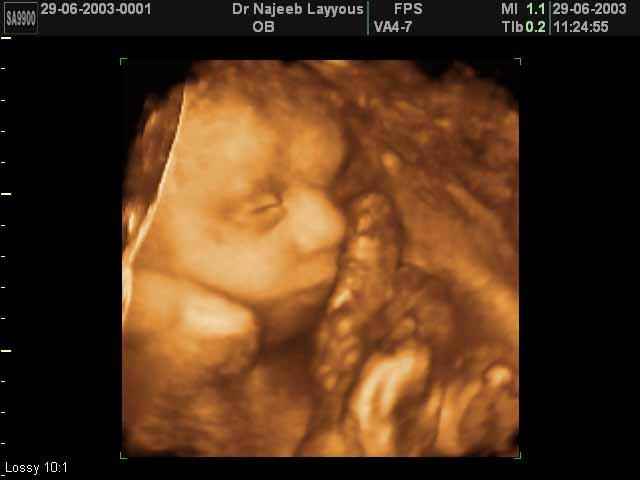

- 3D Fetal Profile Ultrasound Scan Photos

3D Fetal Profile Ultrasound Scan Photos | Dr N Layyous